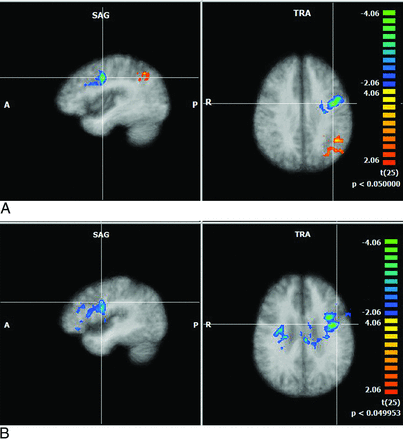

There were significant group differences between the average intercluster correlation in the control and patient groups in the executive network (0.26 versus 0.14, t = 2.6978, df = 25, P = .0123) and salience network (0.52 versus 0.32, t = 2.2372, df = 25, P = .034), indicating that there is significantly reduced synchronicity within these 2 networks (salience and attentional networks) (Figs 1 and 2; Table 3).

Multiplanar and axial depictions of differences between patients with HIV and control subjects in Brodmann area 9 (executive networks) and Brodmann area 13 (salience networks). Positive values represent higher correlation, and negative values depict lower correlation in patients with HIV relative to control subjects. (All the resultant maps are cluster-corrected). A, Brodmann area 9: patients-controls. B, Brodmann area 13: patients-controls.